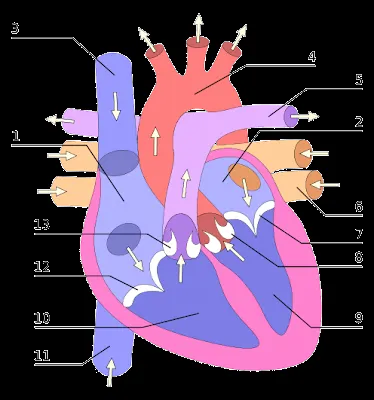

Dibujos del corazón humano

Explora nuestra galería de dibujos del corazón humano, ideales para estudios anatómicos, proyectos educativos y manualidades creativas.

Fotos - El Corazón y sus Partes | Fotos e Imágenes en FOTOBLOG X